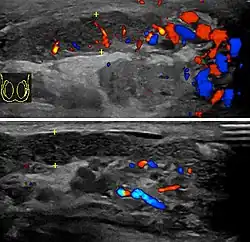

In those who are young and sexually active, gonorrhea and chlamydia are frequently the underlying cause.[1] In older males and men who practice insertive anal sex, enteric bacteria are a common cause.[1] Diagnosis is typically based on symptoms.[1] Conditions that may result in similar symptoms include testicular torsion, inguinal hernia, and testicular cancer.[1] Ultrasound can be useful if the diagnosis is unclear.[1]

Diagnosis is typically based on symptoms.[1] Conditions that may result in similar symptoms include testicular torsion, inguinal hernia, and testicular cancer.[1] Ultrasound can be useful if the diagnosis is unclear.[1]

Epididymitis usually has a gradual onset. Typical findings are redness, warmth, and swelling of the scrotum, with tenderness behind the testicle, away from the middle (this is the normal position of the epididymis relative to the testicle). The cremasteric reflex (elevation of the testicle in response to stroking the upper inner thigh) remains normal.[1] This is a useful sign to distinguish it from testicular torsion. If there is pain relieved by elevation of the testicle, this is called Prehn's sign, which is, however, non-specific and is not useful for diagnosis.[13] Before the advent of sophisticated medical imaging techniques, surgical exploration was the standard of care. Today, Doppler ultrasound is a common test: it can demonstrate areas of blood flow and can distinguish clearly between epididymitis and torsion. However, as torsion and other sources of testicular pain can often be determined by palpation alone, some studies have suggested that the only real benefit of an ultrasound is to assure the person that they do not have testicular cancer.[14]: p.237 Nuclear testicular blood flow testing is rarely used.